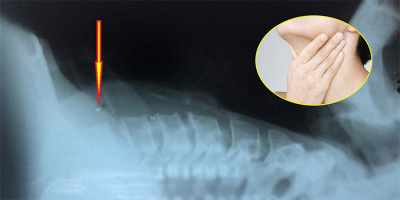

Trị hóc xương

TRỊ HÓC XƯƠNG - Thông tin, tin tức được cập nhật liên tục và mới nhất: